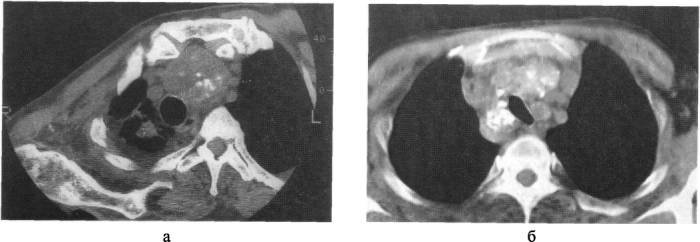

Важно! К наиболее точным и информативным методам диагностики аденомы паращитовидной железы медики относят компьютерную или магнитно-резонансную томографию.

После такой комплексной диагностики специалист может поставить точный диагноз, определить стадию патологического процесса и разработать для пациента оптимальную тактику лечения.